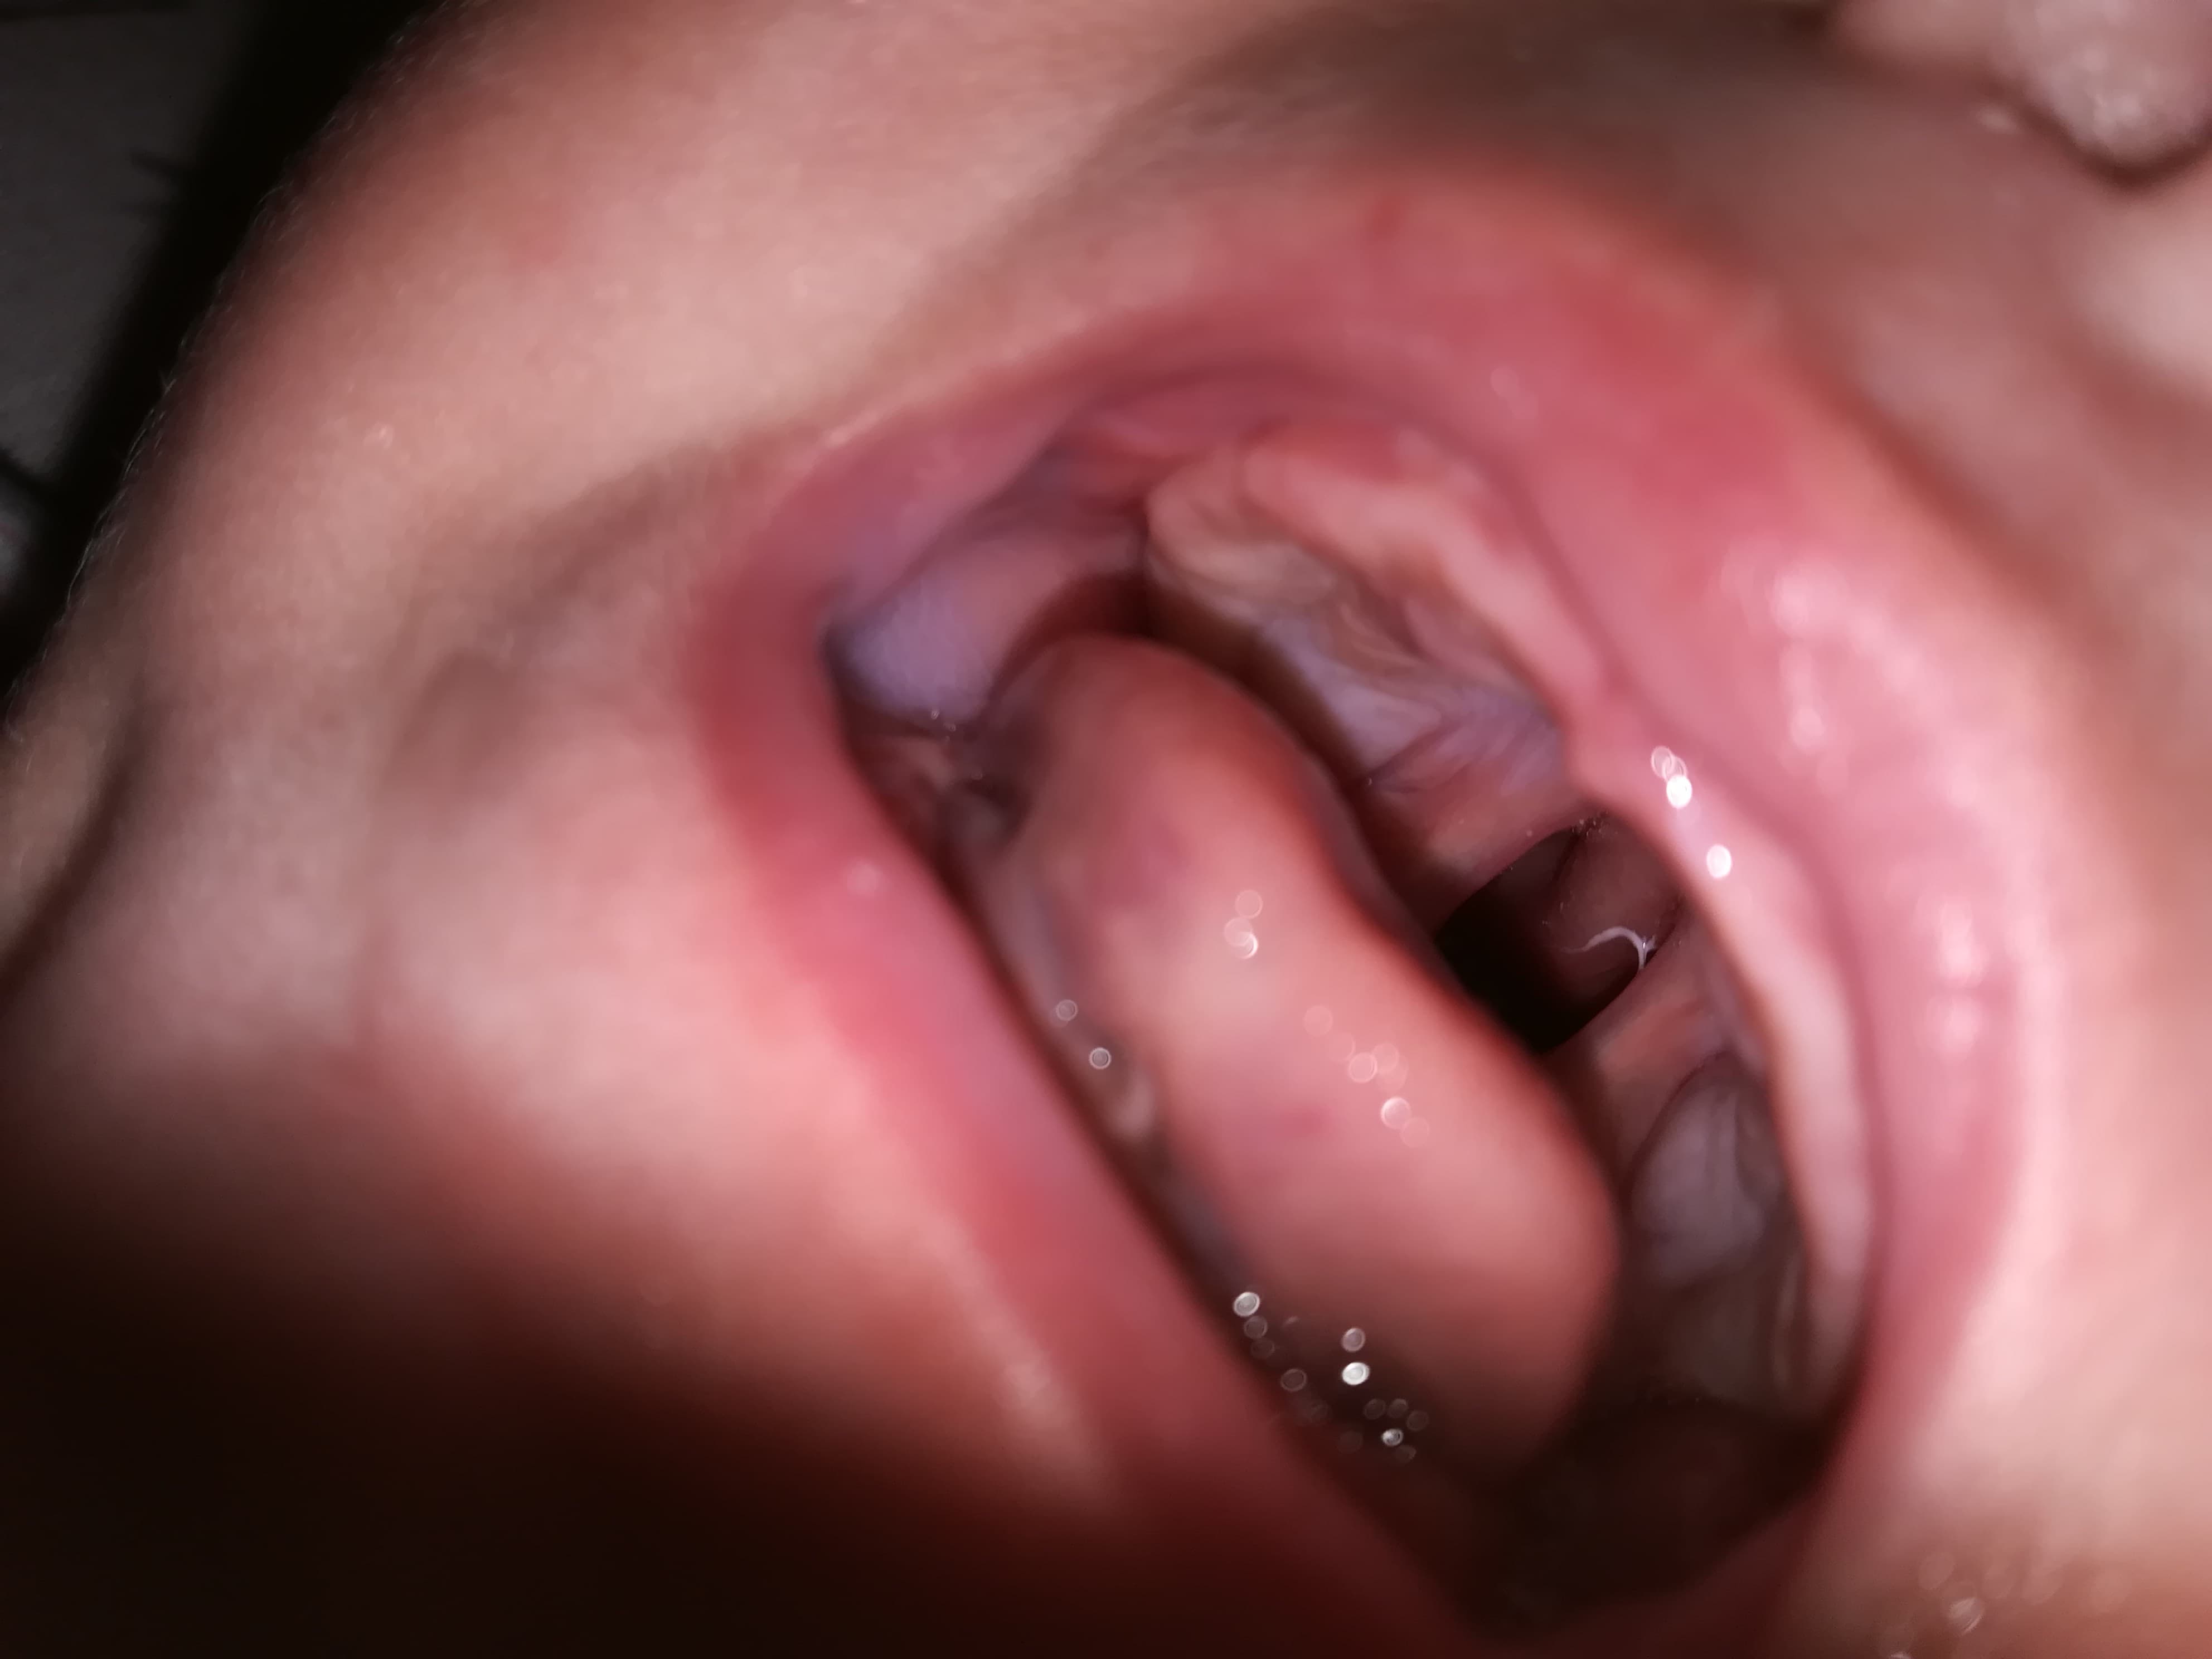

Pe data de 23 iulie s-a născut prințesa lor primul lor copil și atunci au aflat că s-a născut cu o malformație numita palatoschizis. După numeroase vizite/consultări la doctori și cabinete medicale au reușit să aflăm ce înseamnă și ce presupune această problema delicată și că se poate rezolva doar chirurgical, astfel au ajuns sa ia legătura cu un doctor din Italia căruia i-am trimis analizele fetiței pentru a se programa la operație spre finalul lunii decembrie începutul lunii ianuarie.